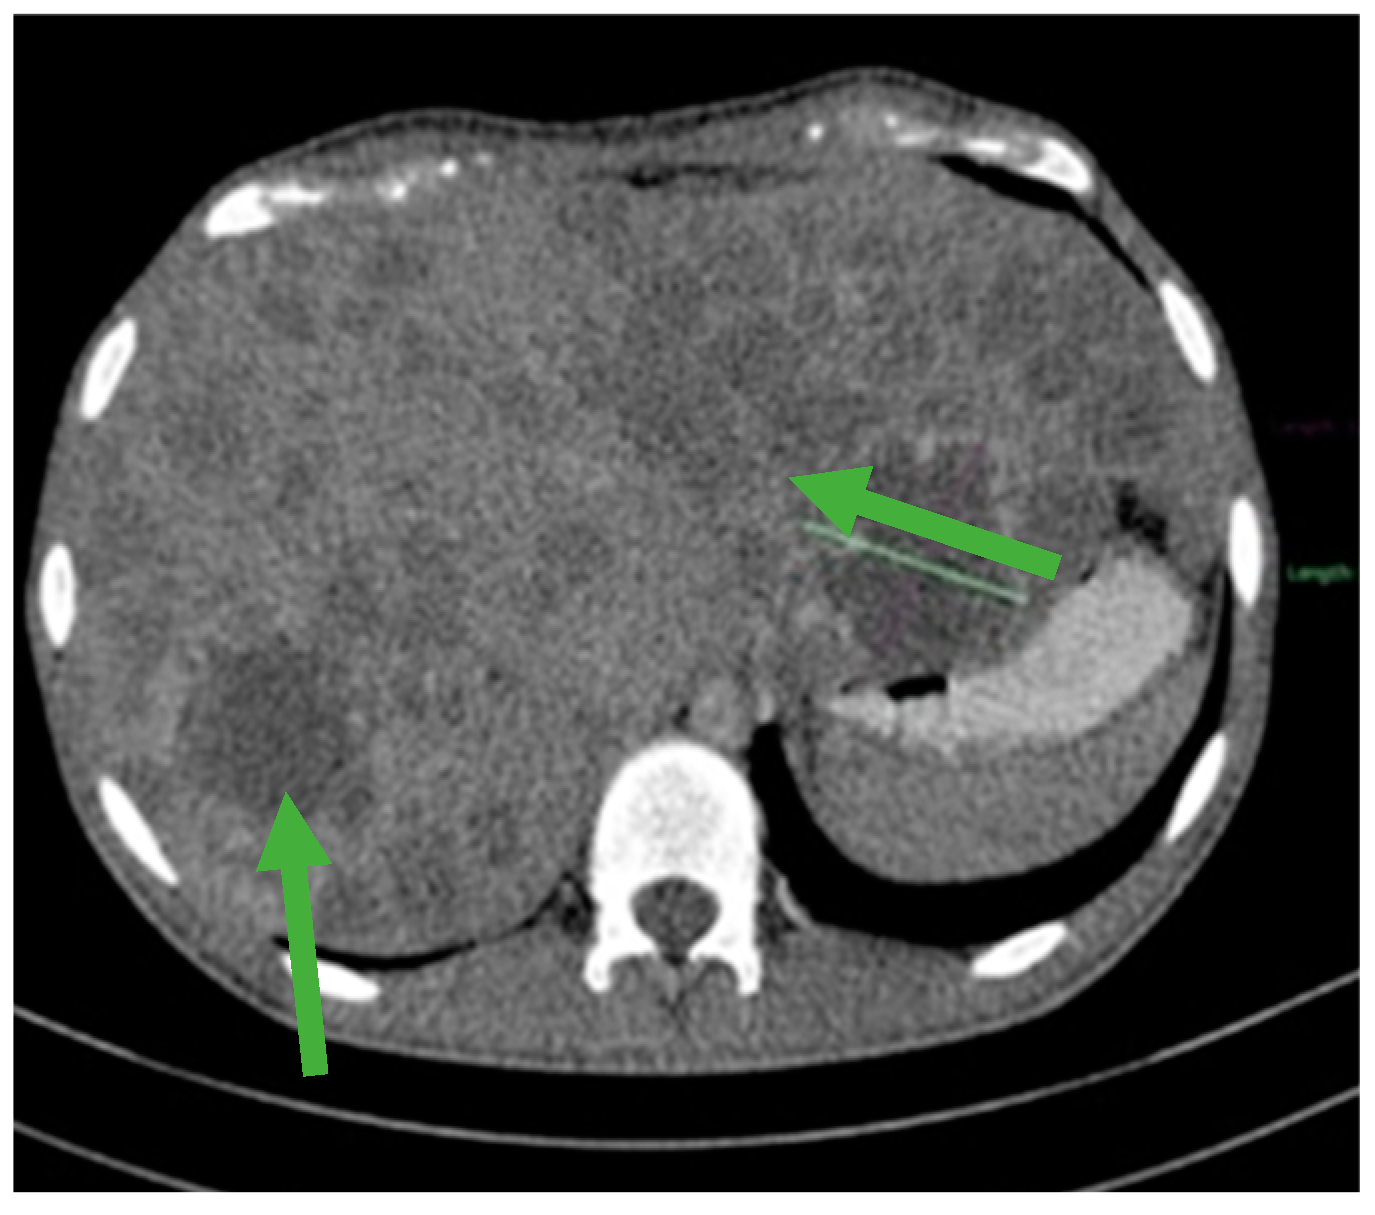

Figure 3.

Hepatomegaly and multiple liver metastases (green arrows).